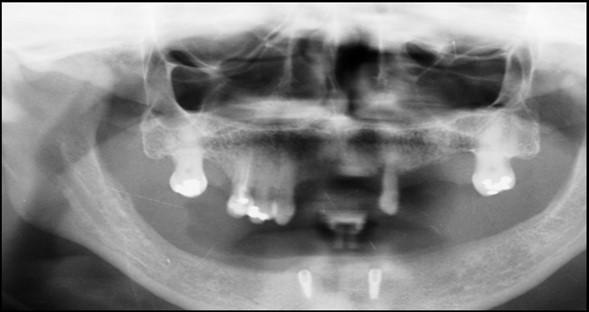

A 63 year old male patient came to our Aesthetics Dental Clinic ,Athens, Greece with the chief complaint of loose fitting lower denture with difficulty in mastication and speech. On examination, patient had resorbed alveolar ridge which lead to inadequate retention of the lower denture prosthesis and patient is known to be a previous denture wearer for past 1 year. The Orthopantomograph findings showed the presence of sufficient bone height and width (Figure 1), with dense cortical bone surrounded by dense trabecular bone. Thus implant supported overdenture was planned with two implants along with independent ball type attachments.

Figure 1.First Visit Pre-operative radiograph

First Visit Pre-operative radiograph